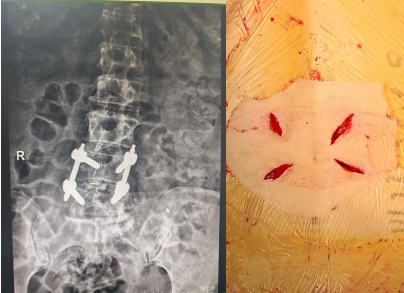

近日,苏州高新区人民医院骨科脊柱微创治疗中心,为一名61岁的女性成功实施了内镜下腰椎滑脱单边双通道脊柱内镜下椎间盘切除,椎管减压,椎间植骨融合内固定术。术后6天患者就可下地。腰疼,下肢放射疼痛症状解除,再次展示出苏州高新区人民医院脊柱外科微创手术的技术实力。

该患者半年前出现腰部及右下肢的疼痛,但休息后尚能缓解最近症状加重,身体出现侧弯,严重影响了日常生活。患者四处求医,但一直因惧怕开放手术的创伤,故一直未选择手术治疗。了解到苏州高新区人民医院一直开展的微创脊柱内镜手术,遂前来就诊,行核磁共振检查后,发现腰4椎体向前明显滑脱,椎间盘突出,椎管狭窄,压迫左侧神经根需要行腰椎滑脱椎间盘切除,椎管减压,滑脱复位,椎间植骨融合内固定手术。医院骨科脊柱微创中心刘勇主任团队为她制定了微创手术方案,腰部创面非常小。

术后患者恢复顺利,术后六天即顺利下地行走,步态正常,原腰疼和下肢疼痛,麻木症状消失,患者对手术效果非常满意。医院脊柱微创中心自2020年成立以来,依托多项微创技术,对脊柱患者尤其腰椎间盘突出症的患者进行微创手术治疗,从单纯的椎间盘突出,椎管狭窄到严重的腰椎滑脱,均可采用微创手术解除患者病痛,为此也树立了良好的口碑。